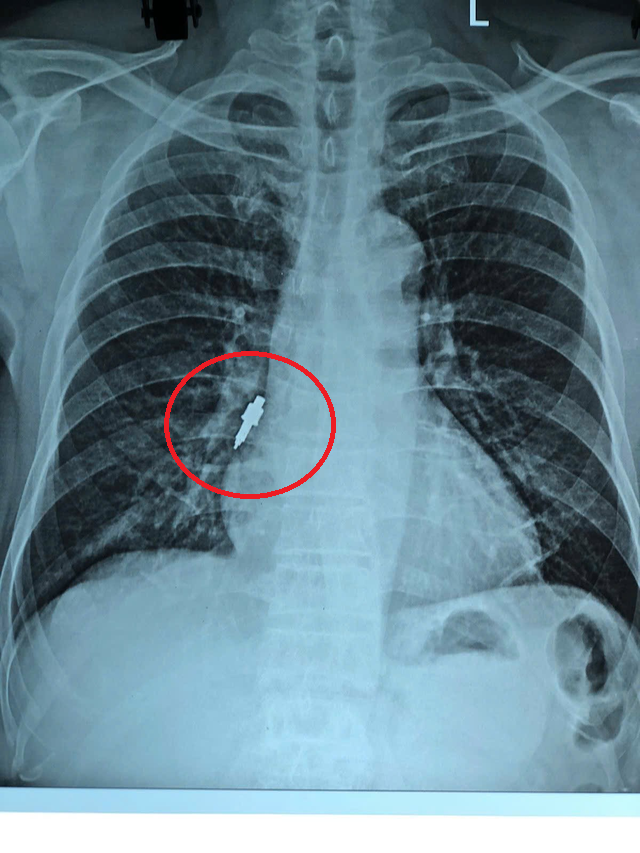

Sau đó, bệnh nhân xuất hiện ho nhẹ kéo dài. Khi cơn ho trở nên dữ dội, gia đình đưa ông đi khám. Kết quả chụp X-quang cho thấy có dị vật nằm trong phế quản phải nên bệnh nhân được chuyển gấp tới Bệnh viện Hữu Nghị.

Tại đây, các bác sĩ quyết định tiến hành nội soi phế quản cấp cứu. Dị vật được xác định bằng inox, bề mặt trơn, đường kính 1cm, dài 2,5cm và mắc sâu vào phế quản phải, kìm sinh thiết thông thường không thể gắp ra.